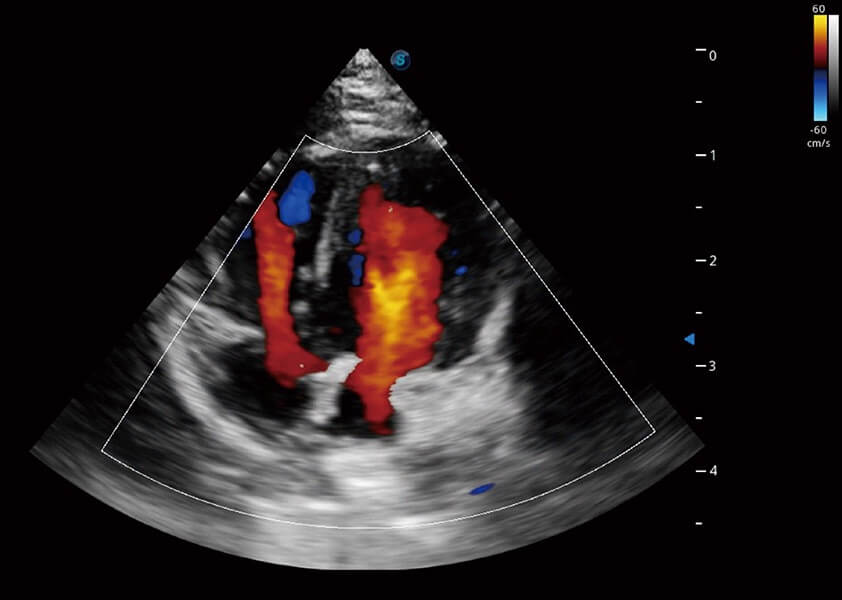

ProPet 60 作为一款高端台式动物超声设备,为动物医生的日常诊断提供了一系列贴合动物临床需求、解决临床实际问题的高级成像功能。凭借全系列高清探头,满足医生对腹部、心脏、生殖、浅表、肌骨等成像的所有需求,切实帮助您提升检查效率,提高诊断信心。

动物是人类最亲密的朋友和最值得信赖的伙伴。新葡的京集团8814检测站也一直致力于探索动物专用的超声影像解决方案。 全新推出的ProPet系列,是新葡的京集团8814检测站在动物超声影像智能化、专业化、精准化的一次跨越式革新。动物不能用言语来表述自己的不适,通过超声影像,ProPet系列搭建了动物医生与不同物种沟通的“桥梁”,为动物医生注入了“治愈之力”。